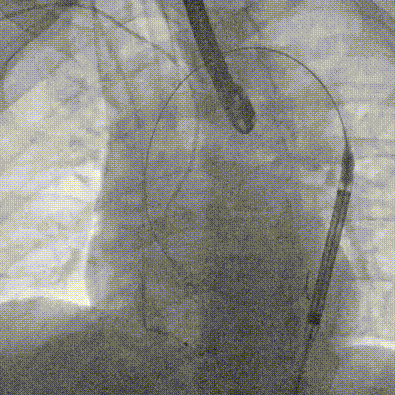

输送系统柔顺过弓

定位

迅速锚定释放至工作位